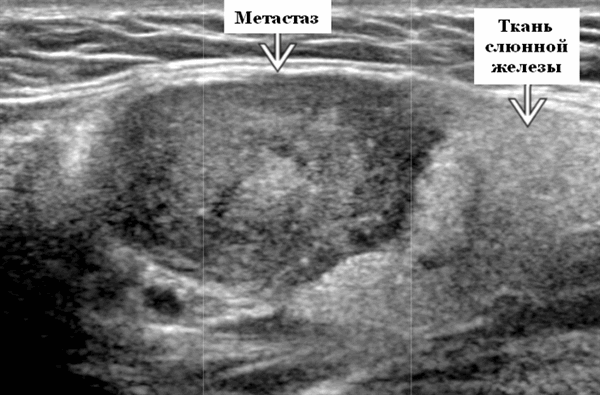

Ключевые факты. Терминология. Лимфатическая или гематогенная опухоль распространяется на внутрижелезистые околоушные лимфатические узлы. Нормальная околоушная железа имеет внутрижелезистые лимфатические узлы, которые определяются на УЗИ (в отличие от подчелюстных и подъязычных желез). Околоушные и перипаротидные узлы: уровень 1-го порядка при плоскоклеточном раке кожи и меланоме волосистой части головы, ушной раковины и лица.

- Одиночные или множественные гипоэхогенные образования при известном распределении внутрипаротидных лимфоузлов.

- На ультразвуковом сканировании образование четко или плохо определено (экстранодальное распространение)

- На УЗИ определяется аномальная внутренняя архитектура ± эхогенные ворота, эхогенность однородная или неоднородная с внутренними кистозными участками в некротических узлах

Визуализация. Общие особенности. Само по себе ультразвуковое сканирование метастазов в околоушные лимфоузлы неспецифична. Одиночные или множественные околоушные образования. Хорошо выраженный или плохо выраженный лимфоузел (экстранодальное распространение), однородный или неоднородный с внутренним некрозом. На УЗИ с ЦДК внутриузловая васкуляризация или усиление кровотока. Патология связана с известным первичным раком, часто в прилегающей коже или региональной области головы и шеи. Околоушные и перипаротидные узлы: узловая станция 1-го порядка при плоскоклеточной карциноме кожи (ПКК) и меланоме латеральной части волосистой части головы, ушной раковины / наружного слухового прохода и передней части лица

Результаты ультразвукового исследования слюнной железы

Серошкальное УЗИ. Одиночные или множественные гипоэхогенные образования в известном распределении внутрипаротидных лимфоузлов. Хорошо выраженный или слабо окаймленный (экстранодальное распространение). Экстранодальное распространение. Обратите внимание на местную инвазию интрапаротидной наружной сонной артерии (ВСА), ретромандибулярной вены или экстрапаротидных мягких тканей. Аномальная внутренняя архитектура ± эхогенные ворота. Однородный или неоднородный вид с внутренними кистозными участками в некротических узлах ± метастазы в шейные лимфатические узлы